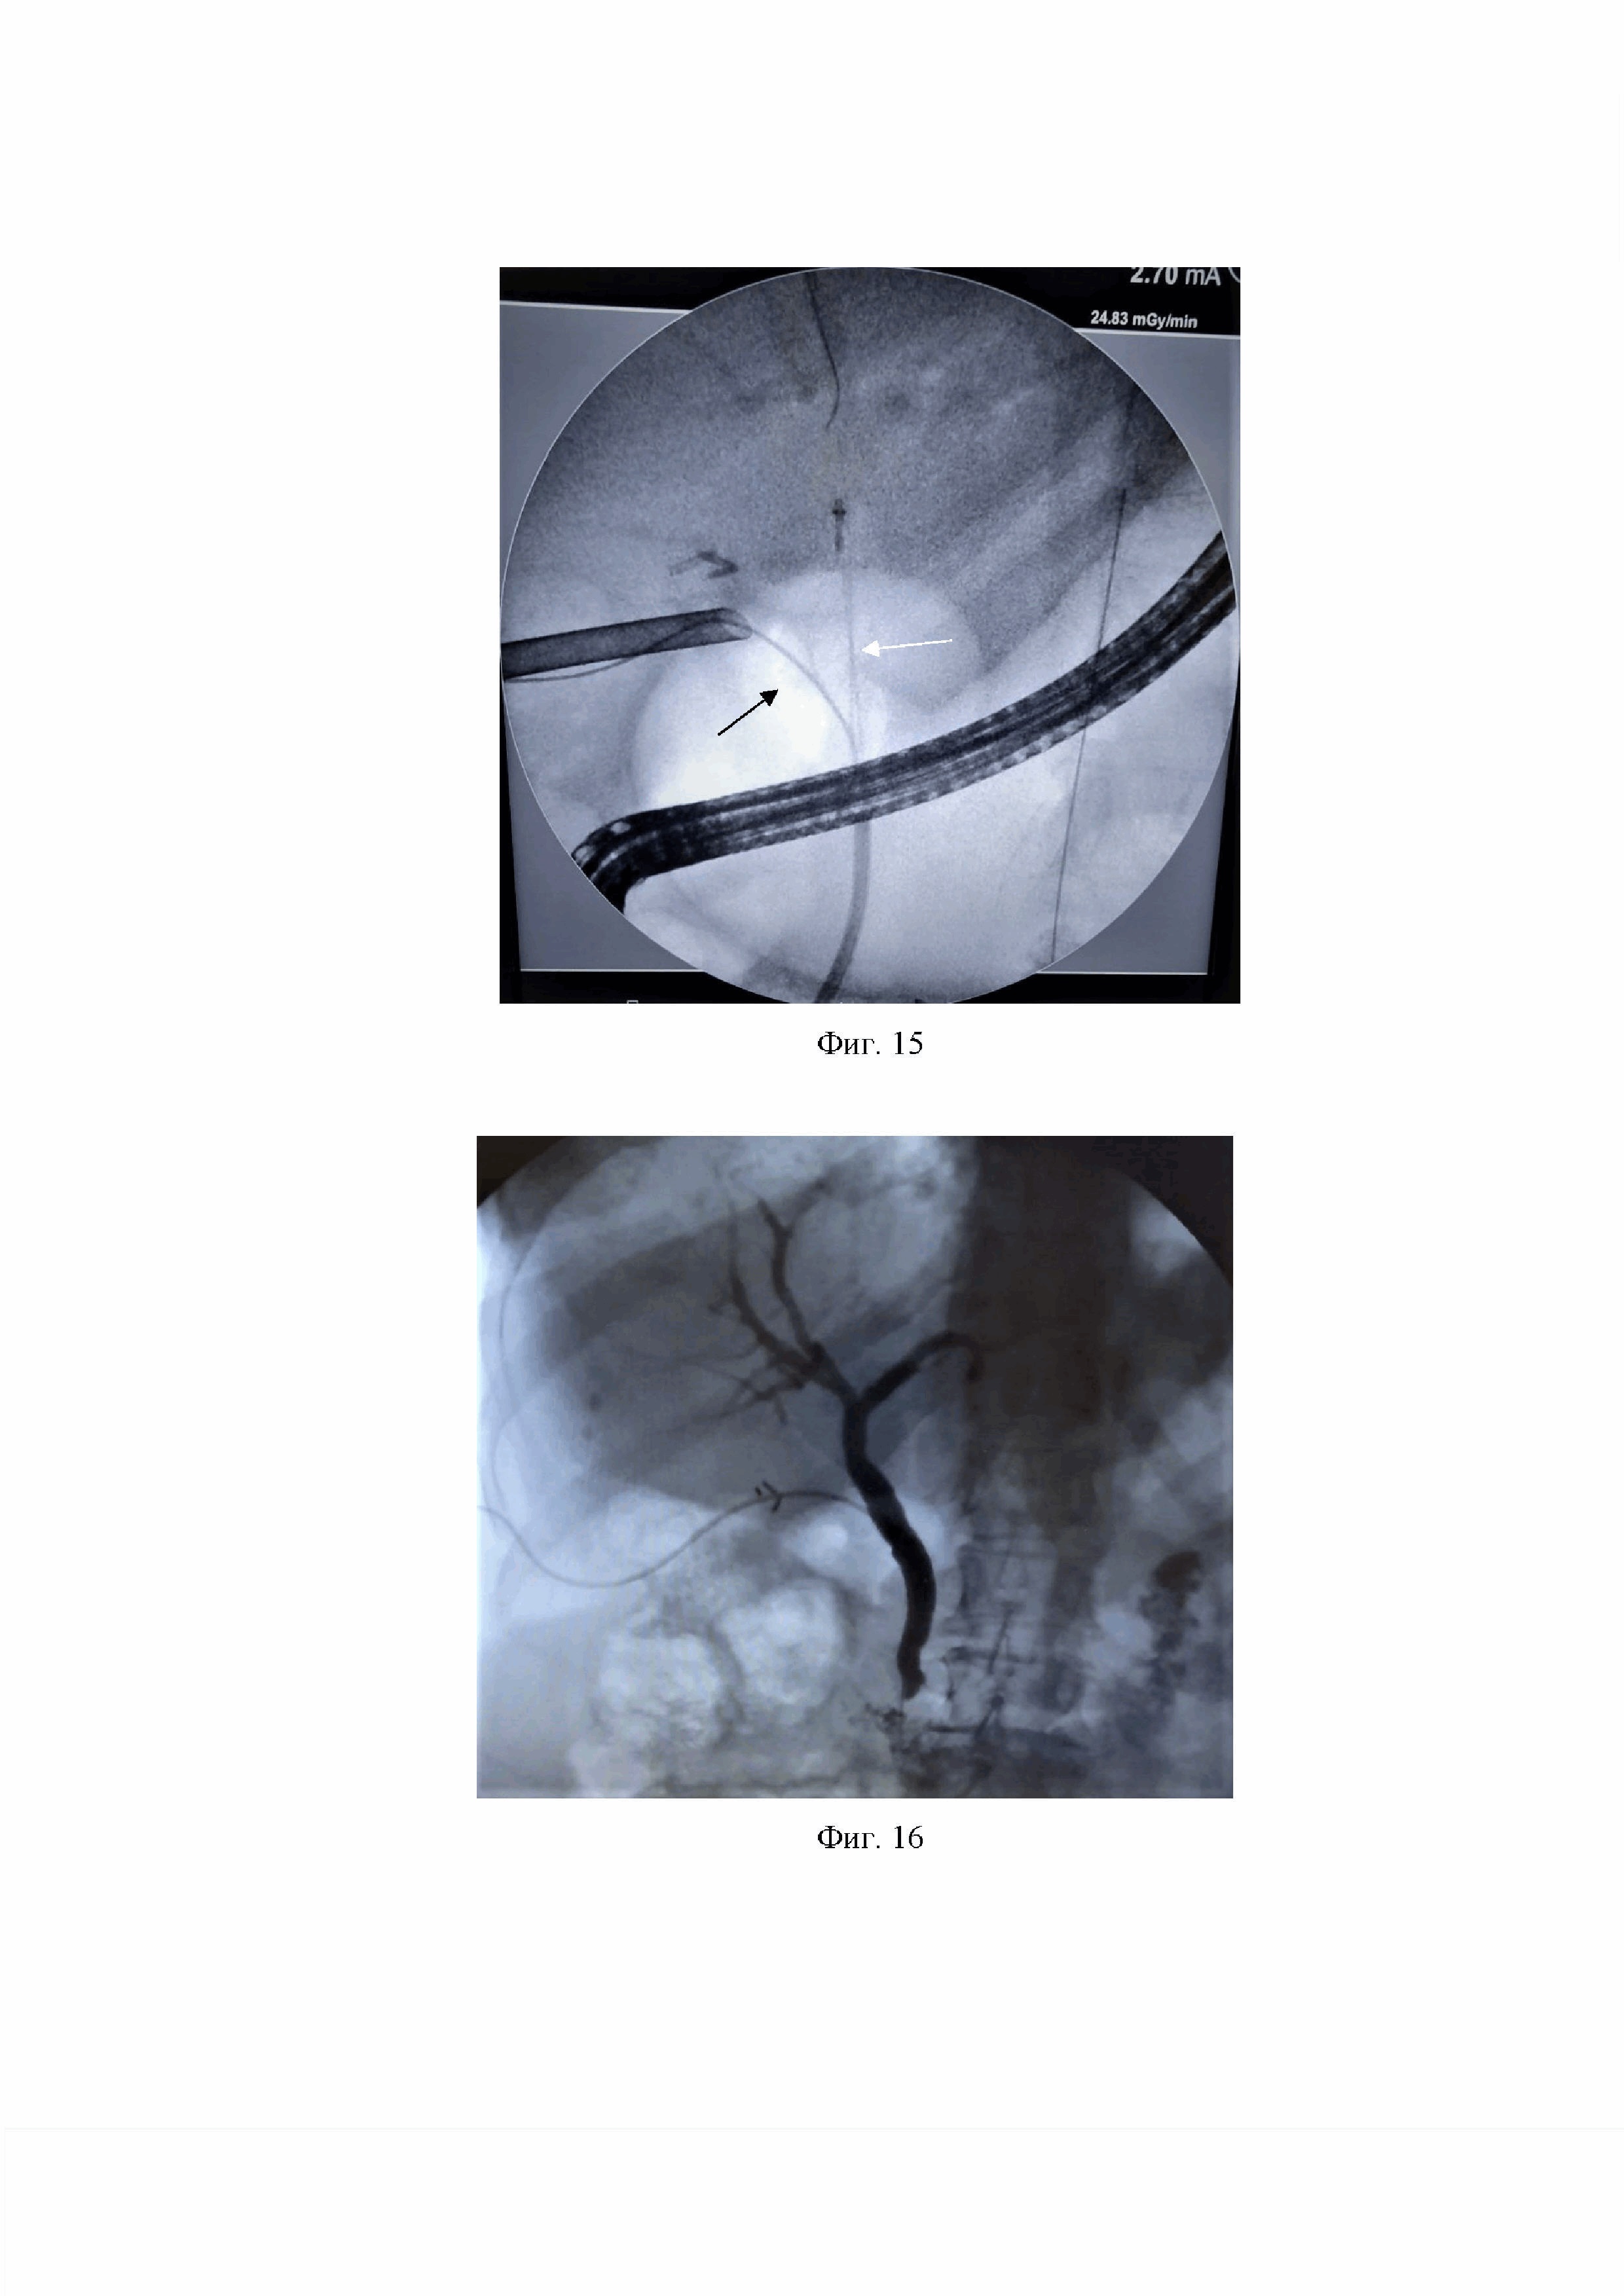

Фиг. 13 Установка ПВХ контрольной дренажной трубки в подпеченочное пространство.

Первым проведён лапароскопический этап, при котором в кармане Гартмана обнаружены конкременты, произведено клипирование пузырного протока и артерии, последняя пересечена, желчный пузырь отсепарован от ложа по методике «от шейки», пузырный проток надсечен наполовину, получена мутная желчь. Подготовлен дренаж Холстеда-Пиковского со сформированным на проксимальном его конце дополнительным отверстием. Через пункционную иглу в правом подреберье в брюшную полость вводится тефлоновый проводник, игла извлекается, производится бужирование хода мягких тканей передней брюшной стенки в месте прокола. Тефлоновый проводник введен через дистальную часть ОЖП и БДС в просвет ДПК, что позволило при эндоскопическом этапе перед РХПГ визуализировать и канюлировать БДС (Фиг. 14).

По низведенному в просвет ДПК тефлоновому проводнику выполнена канюляция БДС (Фиг. 15), произведена РХПГ, в просвете ОЖП визуализированы единичные дефекты наполнения, выполнена ПСТ, корзинкой Дормиа в просвет ДПК извлечены три конкремента коричневого цвета от 5 до 11 мм со сладжем. При контрольной рентгеноскопии дефектов наполнения не обнаружено.

На Фиг. 14 - 16 продемонстрированы холангиограммы этапов хирургического лечения пациентки с ЖКБ, хроническим калькулезным холециститом, осложненным холедохолитиазом и механической желтухой. Фиг. 14 - низведение тефлонового проводника через зону БДС в просвет ДПК. Фиг. 15 - этап эндоскопической канюляции БДС и заведения гидрофильного проводника в желчные протоки (черная стрелка указывает на тефлоновый проводник, установленный антеградно, белая – на гидрофильный проводник, установленный ретроградно). Фиг. 16. - послеоперационный период, дефектов наполнения не определяется.